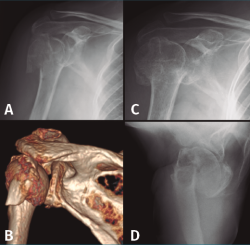

La HA en pacientes en edad laboral es también una opción de rescate ante un fracaso de osteosíntesis o tras una osteonecrosis (Figura 4). Hoy en día podemos encontrar artroplastias modulares que son reconvertibles si fuera necesario a una prótesis invertida sin tener que retirar el vástago. - Prótesis invertidas (RSA). Vistos los resultados no del todo satisfactorios de las HA por la no consolidación de las tuberosidades, se empezaron a colocar RSA en pacientes mayores con fracturas desplazadas, sobre todo en el contexto de roturas del manguito. Con estas prótesis se consigue buenos resultados en cuanto a dolor y una movilidad satisfactoria en pacientes con pocas demandas funcionales. La RSA es una intervención agresiva que deja menos stock óseo en caso de necesitar una revisión. En nuestro grupo de pacientes en edad laboral es muy infrecuente necesitar de entrada resolver una fractura de húmero proximal con una RSA, pero es una opción que tenemos que tener en cuenta. Se han desarrollado también implantes con minivástagos o de apoyo metafisario que permitirían menor pérdida de stock óseo y una revisión menos complicada si fuera necesario.

Figura 4. Evolución radiológica de una osteosíntesis de una fractura de húmero proximal izquierdo. A: radiología preoperatoria; B: osteosíntesis con placa; C: fallo en varo de la osteosíntesis; D: implantación de una hemiartroplastia.